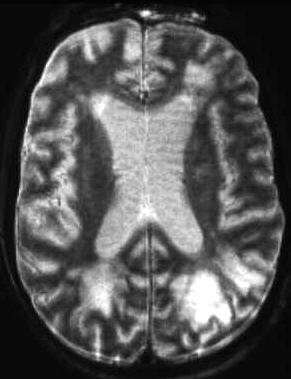

T1-gewichtetes

MRT, T1-gewichtetes MRT nach i.v. KM, T2-gewichtetes MRT:

Transversale

Schnittebene durch das Gehirn in Höhe der Seitenventrikel.

Typische

Bildbefunde:

Das Lymphom

kann sich als solider Tumor, aber auch wie in diesem Beispiel als infiltrativer

Prozess ausdehnen. Hochpathologisch sind die im occipitalen Marklager,

aber auch frontal befindlichen, Signalveränderungen in Kombination

mit Kontrastmittelanreicherungen. Die Liquorräume sind im Rahmen einer

Hirnatrophie erweitert. Es handelt sich um einen Patienten mit erworbenem

Immunmangelsyndrom.